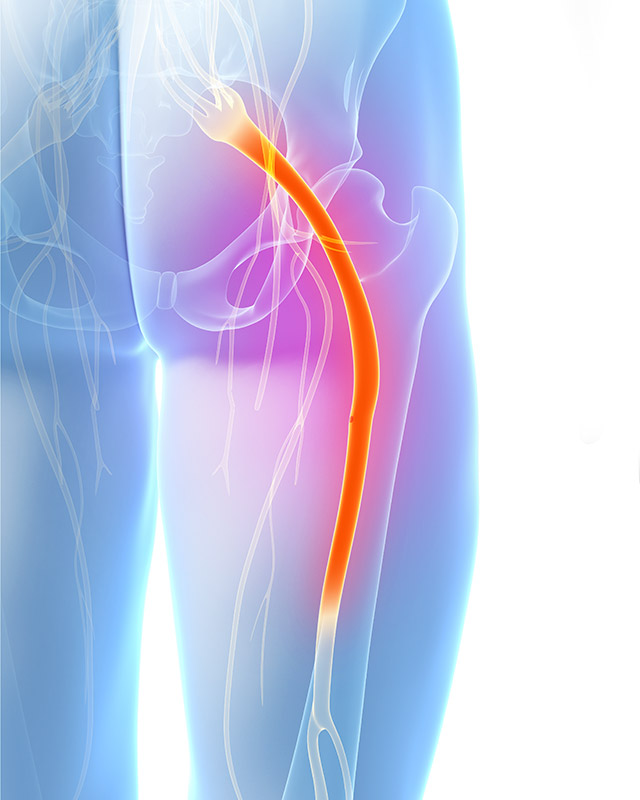

Sciatica

Sciatica is a term used to describe pain that is felt along the sciatic nerve. The sciatic nerve is a large nerve that starts in your lower back. It travels into the buttocks and down the back of the thigh, leg and foot. Irritation to the sciatic nerve can cause a mild discomfort that comes and goes to excruciating pain.

Pain can be felt only in some areas of the nerve distribution or all the way from the low back to the foot. Sciatica is a condition that can have a major impact on the quality of your life. You may not be able to sit for a length of time, therefore driving or sitting at the movies can seem daunting. Often the pain will kick into over-gear at night and will affect your sleep.

Due to the complex nature of the sciatic nerve careful examination and diagnosis is needed. If it looks promising that I can help I will use a combination specific chiropractic techniques to improve the function of the spine and other structures involved.

How long it takes to recover from this condition depends on many factors. The most important thing to remember is that it takes time for the spine to heal. Some patients recover quickly, and others can take weeks or months.

I see people with sciatica regularly. It is one of the main conditions I treat. The best part of treating people with sciatica is not just getting them out of pain but seeing them get their life back.